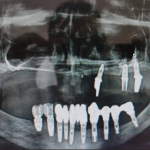

Cas clinique du Dr. Benat avec les implants Ptérygoïdiens

Le patient montre une insuffisance osseuse maxillaire postérieure bilatérale, objectivée sur la radiographie panoramique préopératoire, ne permettant pas la pose d’implants axiaux conventionnels sans solution de rattrapage d’axe.

Avec la collaboration du Dr. Gauthier Benat